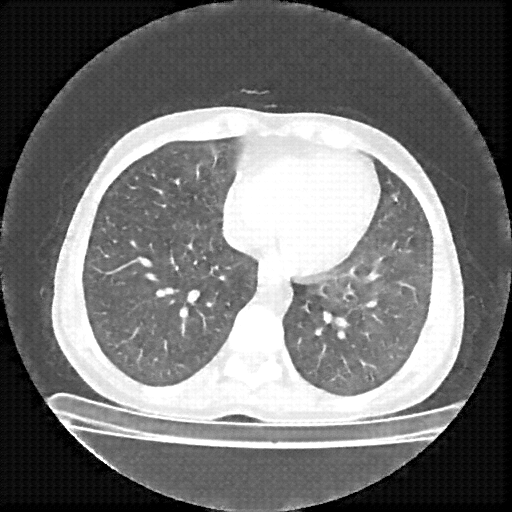

Original NATIVE CT scan (input)

Lung window (WL -600, WW 1500 β†’ Low βˆ’1350, High +150)

Reconstructed NATIVE CT scan (cycle consistency)

Original VENOUS CT scan

Generated VENOUS CT scan (A→B translation)